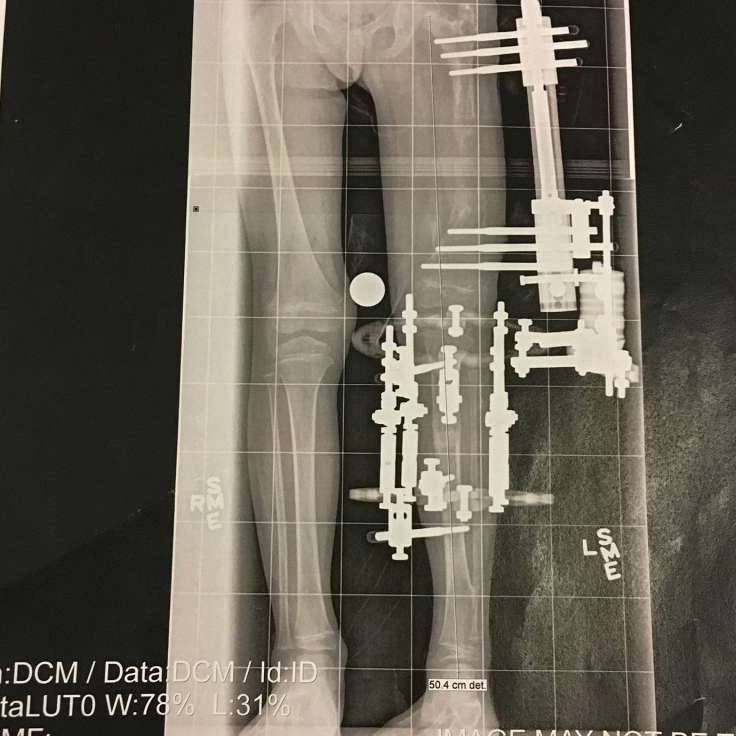

▼4岁女孩莫拉维克(Elsie Moravek)患有先天性股骨发育不全,左脚比右脚短了很大一截。医生告诉她的父母,这样的情况有3种治疗方法,一是截肢;二是装义肢;三就是迫使左腿增长11公分。最后一种方法虽然能够让莫拉维克的外表与普通人无异,但要忍受巨大的痛苦。

▼刚开始,莫拉维克的父母也考虑过截肢,毕竟增长脚骨的过程太痛苦。但他们希望女儿未来有更好的生活,所以选择了最困难的方式。医生为莫拉维克做了长达6小时的手术,在她的股骨和胫骨上装了外部固定器,使用10枝钉子刺穿她的皮肤、肌肉及骨骼。在未来的3个月中,妈妈每天都要转动3次螺丝,拉断她的左腿,迫使骨头生长,防止伤口癒合。

▼经过一段时间的努力,莫拉维克的左腿增长了11公分,现在她的两条腿已经对称,能够走路了。但她的左腿仍旧有缺陷,等她停止长高后,还要再次接受治疗,让左腿继续增长。经过300多次「拉断」治疗,莫拉维克的两腿已经相称,但未来她还需要进一步治疗。